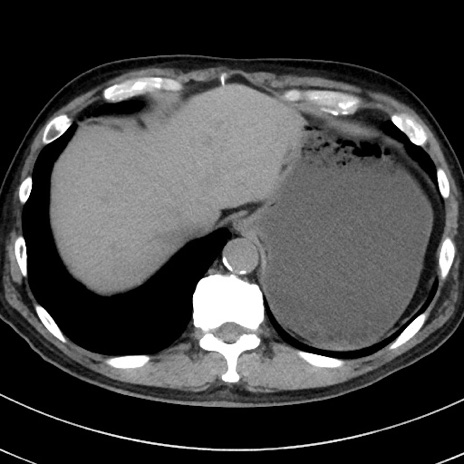

症例38(横断像)

【症例】70歳代 男性

【主訴】腹痛・嘔吐

【現病歴】昨晩より、嘔吐・腹痛あり。今朝になっても嘔吐あり。来院。

【既往歴】心臓バイパス手術、開腹胆摘、腸閉塞

【身体所見】BP 107/71mmHg、HR 116/min、腹部:平坦、軟、下腹部に軽度圧痛あり。反跳痛なし。

【データ】WBC 15100、CRP 0.32